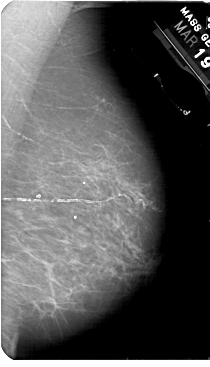

A_1836_1.RIGHT_MLO

RIGHT_MLO LINES 5491 PIXELS_PER_LINE 3136 BITS_PER_PIXEL 12 RESOLUTION 43.5 NON_OVERLAY